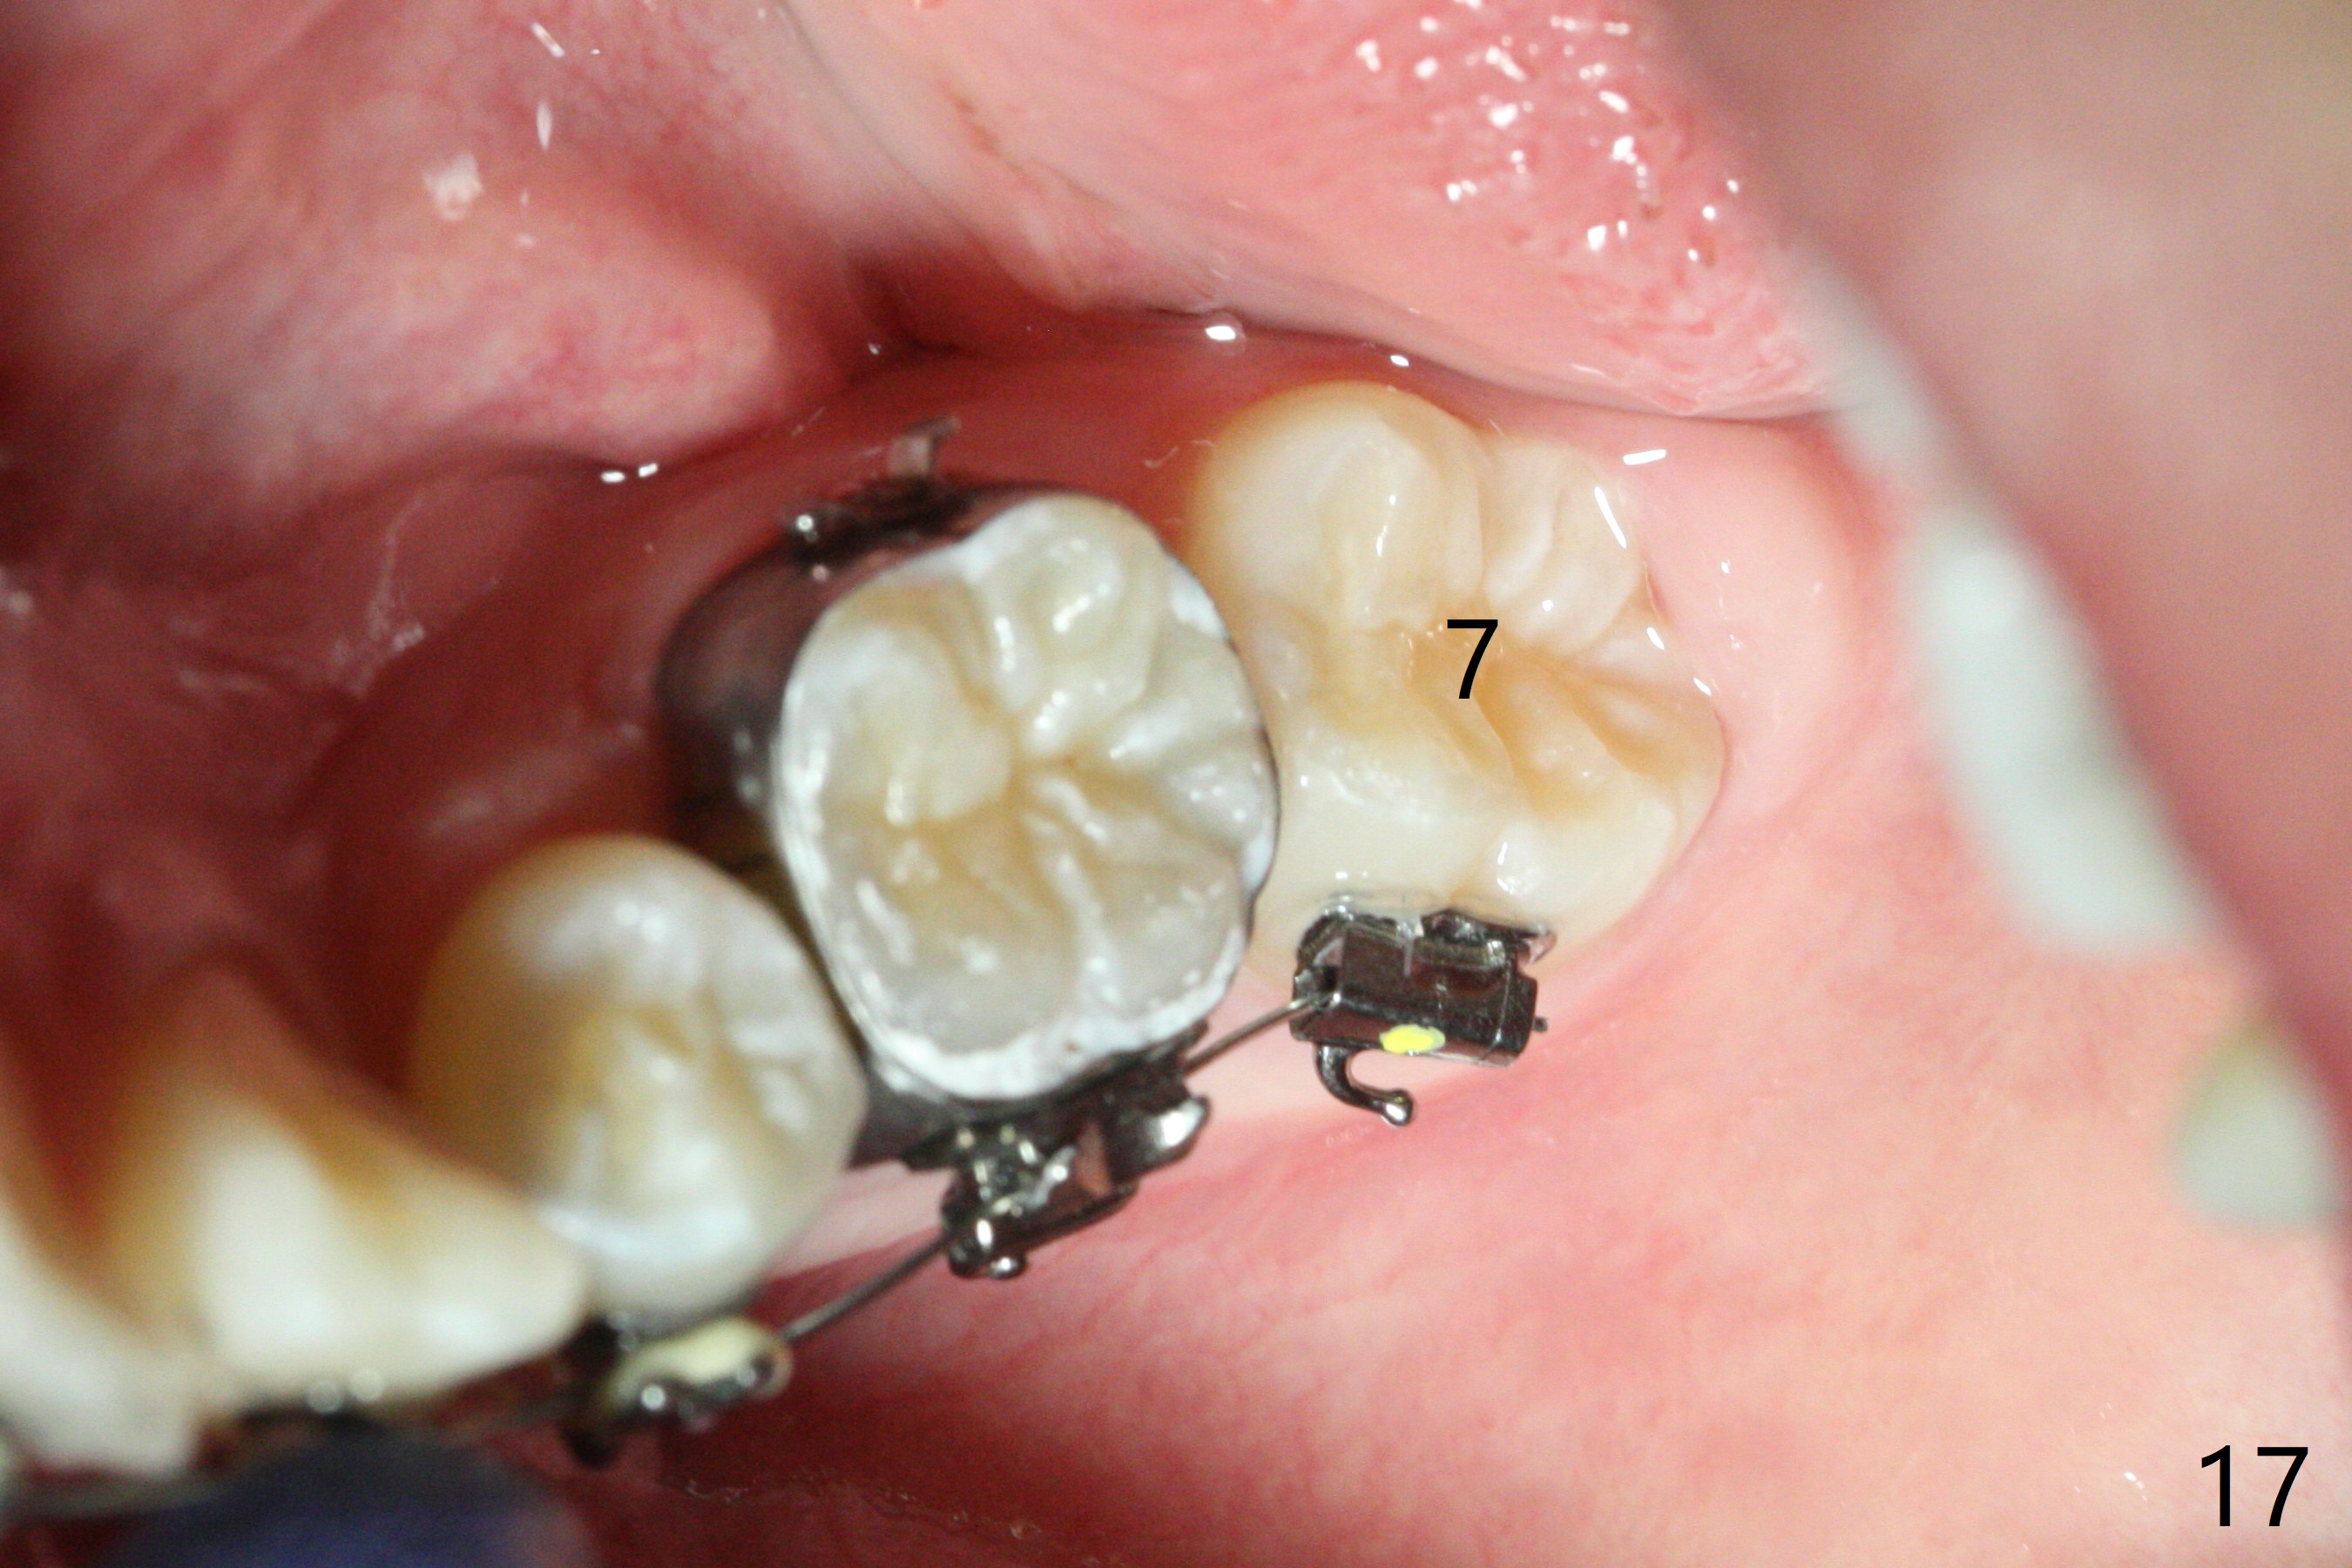

In fact, automatic shifting is striking.  For example, UR5 lingualization (Fig.12 arrow) makes it easy to insert 12 niti wire.  Distalization of the lower bicuspids and canine is more obvious (Fig.13,14 arrows) than the upper counterparts.  Because of incomplete eruption, it is difficult to band L7s; instead brackets are placed (Fig.15-17).  The purpose of LR one is to facilitate LR6 buccalization (Fig.15,16), whereas LL one to correct rotation of itself (Fig.17).